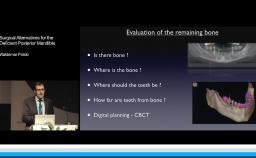

A similar set of rules might also be espoused for implant dentistry. In this presentation, Greg Peake (Periodontist) and Tony Dawson (Prosthodontist) bring a somewhat confronting, occasionally irreverent, and often humorous approach to this topic.

They discuss factors that have the potential to affect the success of implant treatments, and suggest a set of rules that might help us all minimise the risks of complications in the treatments that we provide to our patients.